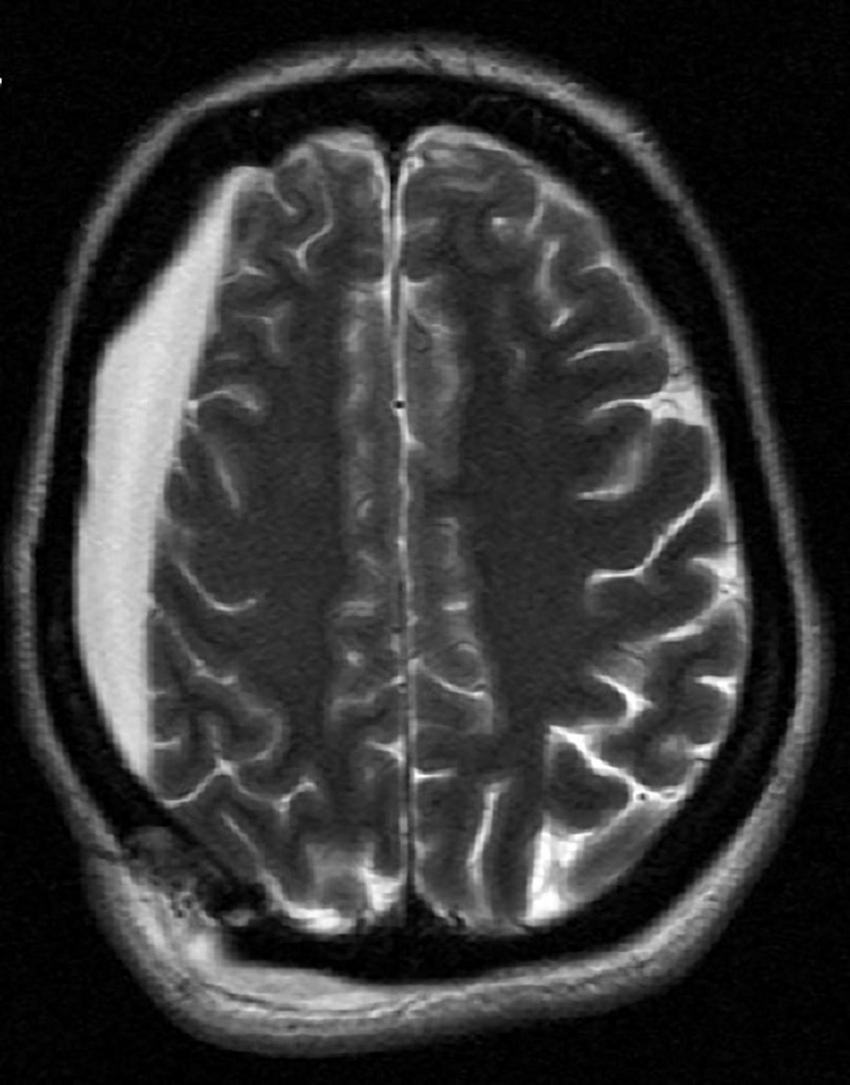

Due to the patient’s prior right craniotomy and subsequent right hygroma (Figure 2), initial ECT sessions were performed with a right anterior, left temporal (RALT) lead placement using a MECTA spECTrum 5000Q ECT Device (9). To maximize cortical recruitment and depolarization to break the SRSE, with or without induction of a seizure, ECT session 1 (total charge dose: 2.0 ms, 3 s, 120 Hz, 800 mA) was performed on day 17 with propofol and ketamine drips paused 30 min before treatment. SE continued so an attempt to induce a seizure with more contemporary parameter settings as seen in psychiatric ECT was utilized. Here the patient was restimulated twice at 60-s intervals using more efficient settings for seizure induction with an ultra-brief pulse width and longer stimulus train to induce a seizure (0.37 ms, 6 s, 120 Hz, 800 mA). ECT session 1 was unable to induce seizures nor halt her baseline seizure activity, and seizure burden continued to increase from 11 to 20% burden over the next 24 h. ECT session 2 was performed with the intensivist team finally agreeing on day 18 to pause ketamine and propofol infusions 2 h prior to the session, having previously been reluctant to do so for fear of worsening SE. Session 2 consisted of four stimulations each separated by 60 s, with the first two using 1 ms, 6 s, 60 Hz, 800 mA and the latter two stimulations using 2 ms, 3 s, 60 Hz, 800 mA. Shorter pulse widths were not used as these settings would have prevented 100% of the total device energy that was to be used. ECT session 2 induced transient epileptiform activity with burst suppression but was then followed by an almost immediate return to baseline SE. Seizure burden continued to increase to 30% despite a combination of treatments. ECT session 3 was performed on day 19, now with ketamine and propofol infusions paused 3 h before the session. It consisted of one stimulus at 0.5 ms, 3 s, 60 Hz, 800 mA with a 3-min hiatus followed by 1 ms, 3 s, 60 Hz, 800 mA. The final stimulus attempted to maximize interelectrode distance with bitemporal lead configurations (Table 1). ECT session 3 again induced mild epileptiform activity with subsequent return to baseline without meaningful change in seizure burden post-ECT stimulus. The VNS remained on during ECT as the primary team was reluctant to turn the device off; VNS interrogation following ECT treatments showed its proper functioning. In discussion with the epileptologist and neurologic critical care team, as the seizure burden had continued to steadily worsen over the course of the patient’s illness, and with only mild transient encephalographic (EEG) changes from ECT treatment, the decision was made to discontinue ECT treatment. The patient’s family opted for comfort care measures, and the patient died on day 24.

Figure 2. Magnetic resonance imaging showing patient’s right hygroma prior to initiation of electroconvulsive therapy (ECT).

Initial electrode placement was RALT. This placement was used to avoid the region with underlying cortical pathology, i.e., the chronic hygroma. RALT allowed for reasonable interelectrode distance. This is opposed to an idealized placement of the stimulating electrodes immediately over a solitary seizure focus, which is impractical given the extreme shunting of electricity through the scalp that would arise through reducing the interelectrode distance. Such shunting and current spreading via the scalp, and the skull’s high resistance, during electrical stimulation is a known problem that can interfere with ECT. Novel approaches for seizure induction such as Magnetic Seizure Therapy attempt to resolve this issue (16). When multiple attempts at this placement failed, we proceeded with bitemporal ECT despite its positioning the electrical field bilaterally across the cortex, and over the hygroma. This placement was selected to maximize interelectrode distance in an attempt to minimize interelectrode shunting through the scalp. Unfortunately, bitemporal ECT also failed to terminate status in this patient.